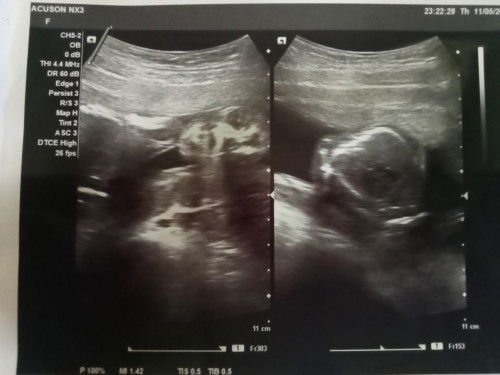

ซาวด์เพศลูกที่ไหนกันบ้าง

แม่ๆคนไหนที่ได้ฝากรพ.รัฐบ้างค่ะแล้วเขาซาวด์ให้อะค่ะ ที่แม่ไปฝากเขาบอกว่าจะไม่ซาด์เพศให้ต้องไปซาวด์ที่คนิกเอาเองเสียตังอะค่ะตอนนี้30+1ยังไม่รุ้เพศเลยค่ะ#ขอบคุณล่วงหน้านะคะ

แม่ๆคนใหนดูออกบ้างมั้ยค่ะ อิแม่งงเป็นไก่ตาแตกเลยค่ะ